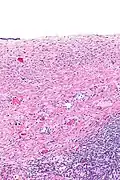

Histopatología

Los cistoadenomas serosos se diagnostican mediante examen histomorfológico, por patólogos. En general, son quistes uniloculares que contienen un líquido claro de color pajizo. Microscópicamente, el revestimiento del quiste consiste en un epitelio simple con cilios que puede ser columnar o plano.

Imágenes microscópicas